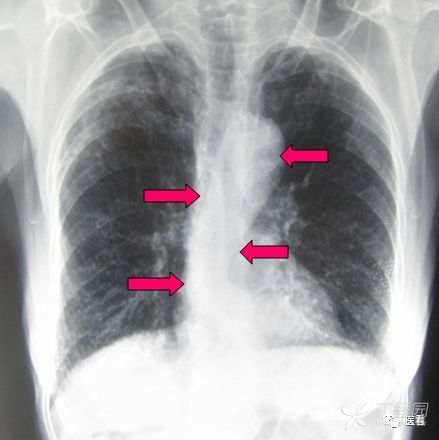

乳腺成形术或丰胸术后

尤其是患者隐瞒病情,或单侧手术时,需要注意鉴别。

辨识方法:充填物区无正常乳腺组织结构,呈密度均匀的无结构影(红箭)。注意双侧对照,或与正常人乳腺图像对照。